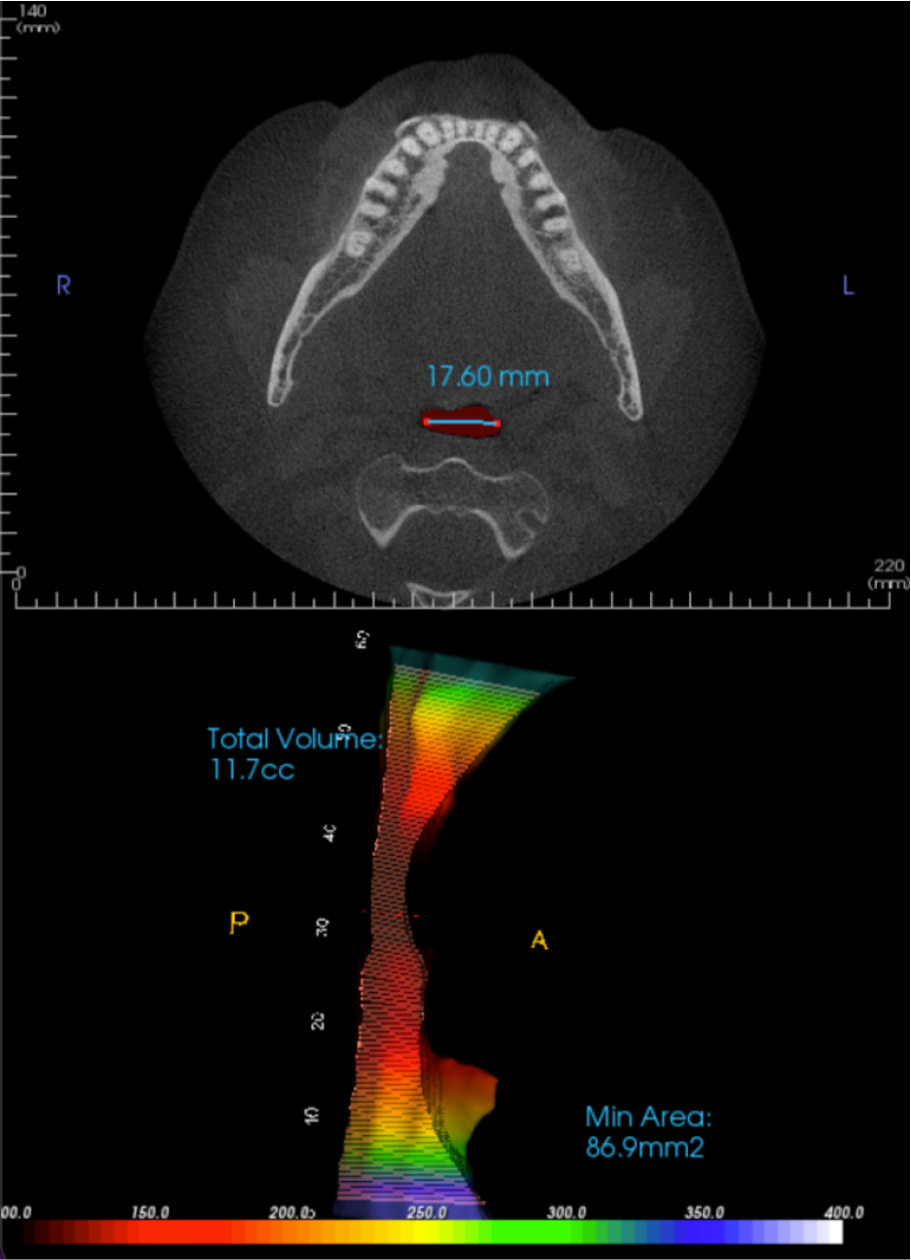

CBCT Imaging Evaluation